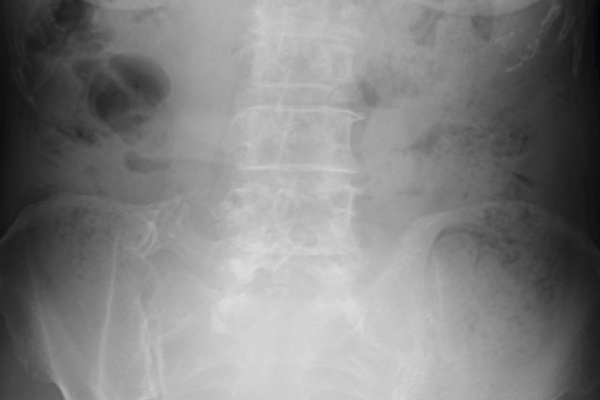

左下腹部痛を主訴とした50歳代男性 実践 画像診断q A 羊土社 レジデントノート 羊土社